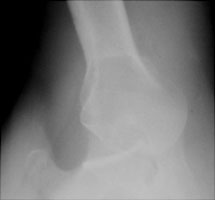

Posterior dislocations of the humerus account for less than 5 % of shoulder dislocations and are usually due to direct force. Classically, the causes are seizure or electric shock. The axillary view is the best view to demonstrate this type of dislocation.

- Click on the image for a larger versionAAP radiograph of the right shoulder. A cursory examination reveals no obvious dislocation.

- Click on the image for a larger versionBAxillary radiograph. Notice the anterior coracoid with the posteriorly dislocated humeral head relative to the glenoid.